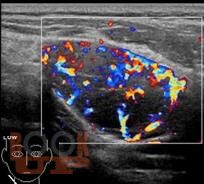

Учебное пособие посвящено ультразвуковой диагностике образований шеи, больших слюнных желез и лимфатических узлов. Подробно рассмотрены методологические аспекты применения мультипараметрического ультразвукового исследования слюнных желез и лимфатических узлов в норме и при различных заболеваниях, редкой патологии - врожденной сосудистой мальформации на шее. В конце пособия приведены вопросы и ответы для самоконтроля.